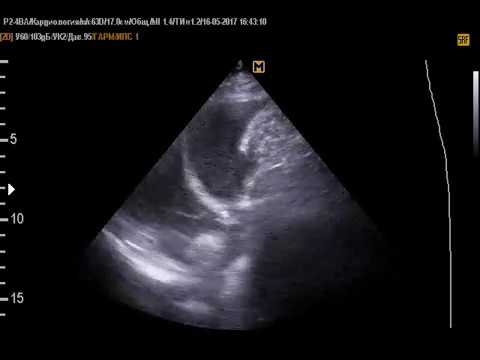

Смотрите дополнительно видео, где в плевральной полости видно жидкость:

В протоколе УЗИ описано фактическое состояние правой и левой плевральной полости. При норме поверхность легкого отражается в виде широкой белой полосы (из-за воздуха в альвеолах). Орган по контуру покрывает гипоэхогенная линия толщиной 0.4―1 мм. Это плевра. Если нет патологий, она темно-серая или черная, подвижна во время дыхания, плотно прилегает к легочной ткани.

Развитие патологий меняет структуру и толщину оболочки, объем щели. Жидкость в плевральной полости может содержать серые и белые вкрапления, скапливаться в одном месте. При новообразованиях деформируется контурная линия легких, есть очаги с измененной эхогенностью.